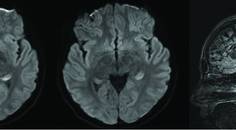

Video-Case Report: Progressive Neuropathy With Cerebellar Ataxia